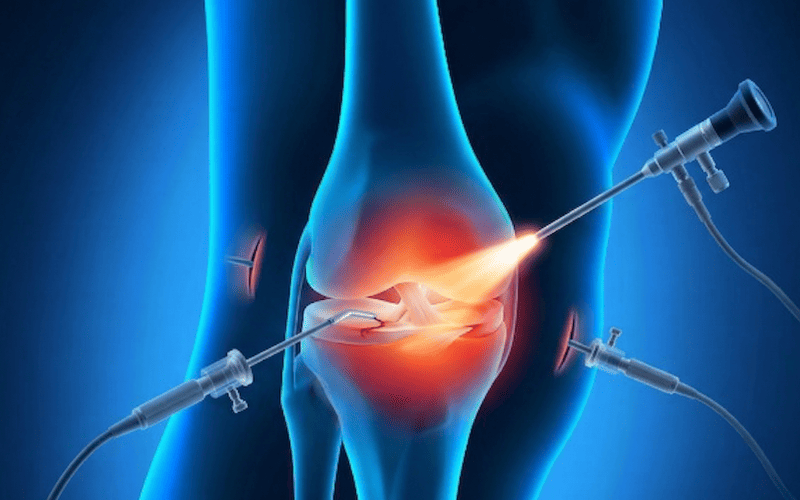

Exploration et traitement articulaire mini-invasif du genou par arthroscopie diagnostique et opératoire.

Reconstruction du LCA par ligamentoplastie sous arthroscopie. Techniques DIDT et Kenneth-Jones.